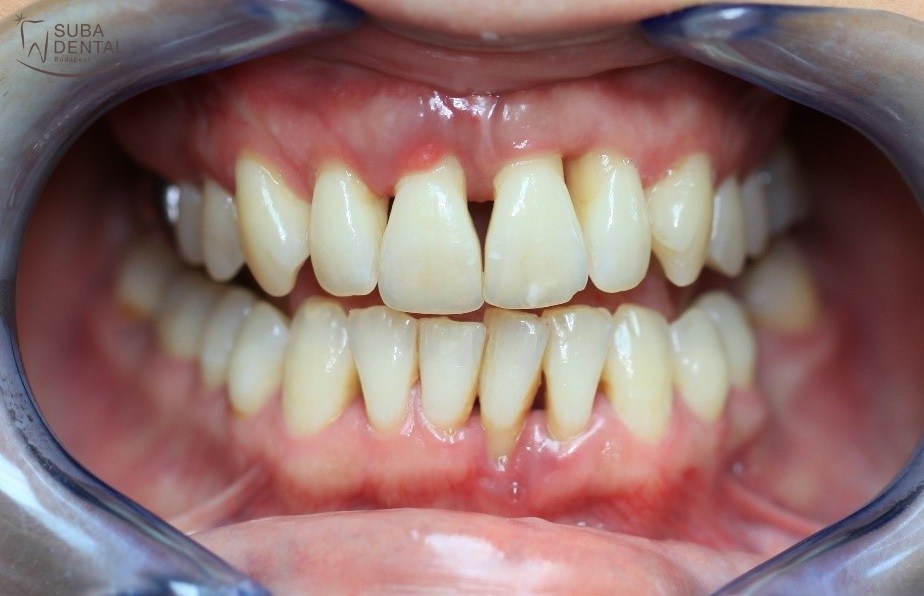

- Úgy érzi, hogy gondok vannak frontfogaival. Fogínye nagyon visszahúzódott, fognyaki érzékenységre panaszkodik, és fogai nagyon mozognak.

- A fogai közti fekete lyukak nagyon zavarják.

Fotó a fogak eltávolítása előttről